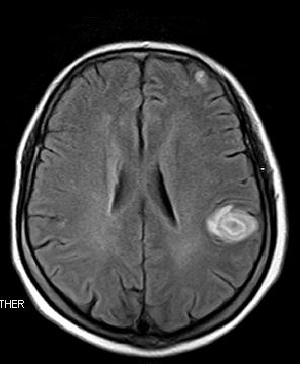

2年后出现脑多发转移(磁共振)